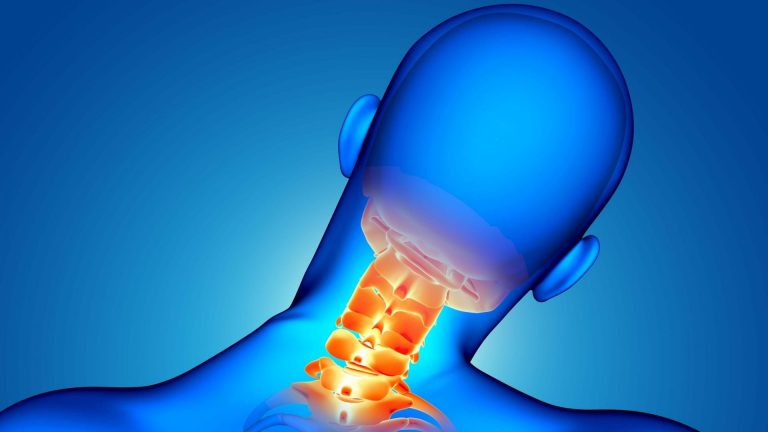

ستون فقرات، بهعنوان محور اصلی حرکت و پشتیبانی بدن، تحت تاثیر عوامل مختلفی، ممکن است دچار فرسایش و التهاب شود. آرتروز ستون فقرات، که به آن اسپوندیلوز نیز گفته میشود، یک بیماری دژنراتیو است که با تحلیل رفتن غضروف مفاصل و دیسکهای بین مهرهای همراه است. این فرایند میتواند...

دیسک گردن یکی از مشکلات شایع در دنیای امروز است که میتواند کیفیت زندگی فرد را به شدت تحت تاثیر قرار دهد. معمولا دردهای گردن به دلایل مختلفی از جمله آسیب، ضربه، آرتروز، یا مشکلات دژنراتیو دیسکها ایجاد میشود. این دردها ابتدا ممکن است در ناحیه گردن احساس شوند،...

فتق یا بیرون زدگی دیسک یکی از مشکلات شایع ستون فقرات است که به دلیل فشار یا پارگی در دیسکهای بین مهرهای ایجاد میشود و باعث درد، بیحسی و ضعف در اندامها میشود. معمولا افرادی که بیشتر از ۳۰ سال دارند دچار این بیماری میشوند، اما سن تنها عامل...